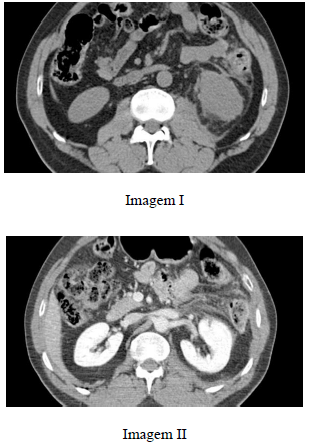

Paciente do sexo masculino, com 37 anos de idade, após cair de uma árvore de 6 m de altura, refere dor lombar à esquerda e hematúria. Realizou tomografia computadorizada de abdome, que evidenciou as imagens I e II a seguir.

A imagem I demonstra infiltração do espaço perirrenal e do espaço pararrenal posterior à esquerda.

A imagem II mostra uma laceração no rim esquerdo que se estende até a pelve.

O material hipodenso perirrenal à esquerda tem como diagnósticos diferenciais sangramento ou extravasamento de urina, cuja pesquisa não é possível de ser realizada por meio de tomografia computadorizada.